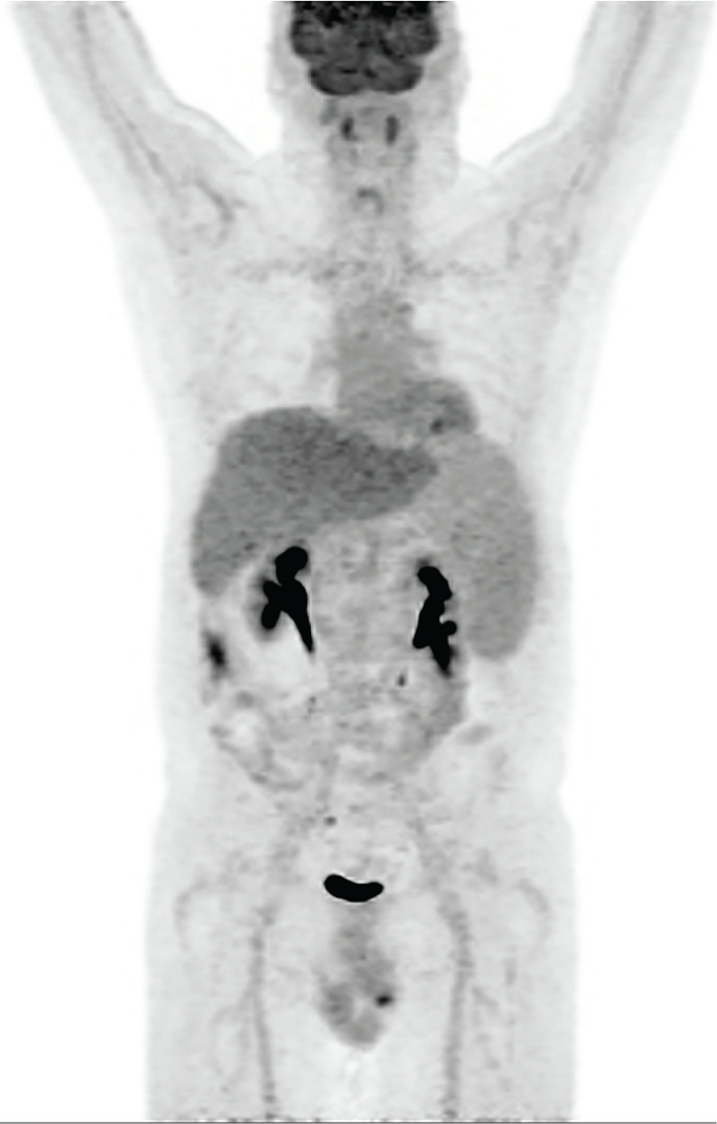

This radiopharmaceutical requires the patient’s own blood for labeling of autologous leukocytes. Following labeling, care must be taken to ensure that the same patient receives its own labeled leukocytes. This can be a challenge, especially if more than one patient is being evaluated with labeled leukocytes on the same day. The mechanism of localization is direct visualization of the infectious process due to accumulation of radiolabeled leukocytes. 111In has a 67-hour half-life, is cyclotron produced, and decays via electron capture. The photopeaks are 173 keV and 247 keV. Patients need to have adequate blood counts for appropriate labeling, with a minimum of 4,000 white blood cells. To label the leukocytes, about 20 mL of blood is withdrawn and is usually sent to a central radiopharmacy for radiolabeling, then returned the same day for injection. The normal biodistribution of 111In-oxine -labeled leukocytes is shown in Figure 2. Importantly, 111In-oxine labeled leukocytes do not have normal activity in the urinary tract or gastrointestinal tract, so if infection is suspected in the abdomen, this would be the labeled leukocyte of choice (2). Labeled leukocytes can also be used in applications such as the diabetic foot and Charcot joint to evaluate infection, along with additional or potentially concomitant dual isotope imaging (if performed with 111In-oxine labeled leukocytes) with 99mTc-sulfur colloid bone marrow imaging. This has a sensitivity and specificity rivaling that of magnetic resonance imaging (MRI). MRI often is difficult to interpret in the setting of diabetic foot and Charcot joint infections. Labeled leukocytes are poor at detecting vertebral osteomyelitis (3) and somewhat less poor at detecting etiologies of fever of unknown origin (46). FDG PET/CT outperforms in this setting.

Fig 2

Figure 2 Normal biodistribution of radiolabeled leukocytes. A. 99mTc-HMPAO labeled leukocytes, and B. 111In-oxine labeled leukocytes. Note the lack of GI tract and urinary tract activity on the 111In-oxine labeled leukocytes.

99mTc-HMPAO-LABELED LEUKOCYTES

This radiopharmaceutical also requires the patient’s own blood for labeling of autologous leukocytes with similar requirements for number of leukocytes and labeling process as 111In-Oxine labeled leukocytes. Similar care with delivery of the labeled leukocytes to the correct patient should be employed. 99mTc has a half-life of 6 hours and a photopeak of 140 keV, decaying by isomeric transition (7). 99mTc-HMPAO-labeled leukocytes will have normal activity in the bowel and urinary tract. Normal biodistribution is shown in Figure 2.